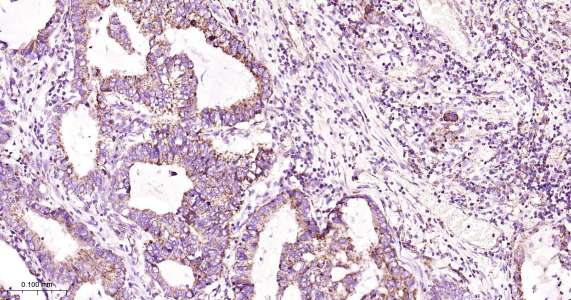

Immunohistochemical analysis of paraffin embedded human lung cancer tissue slide using IHC0443H (Human MtTF1 IHC Kit).